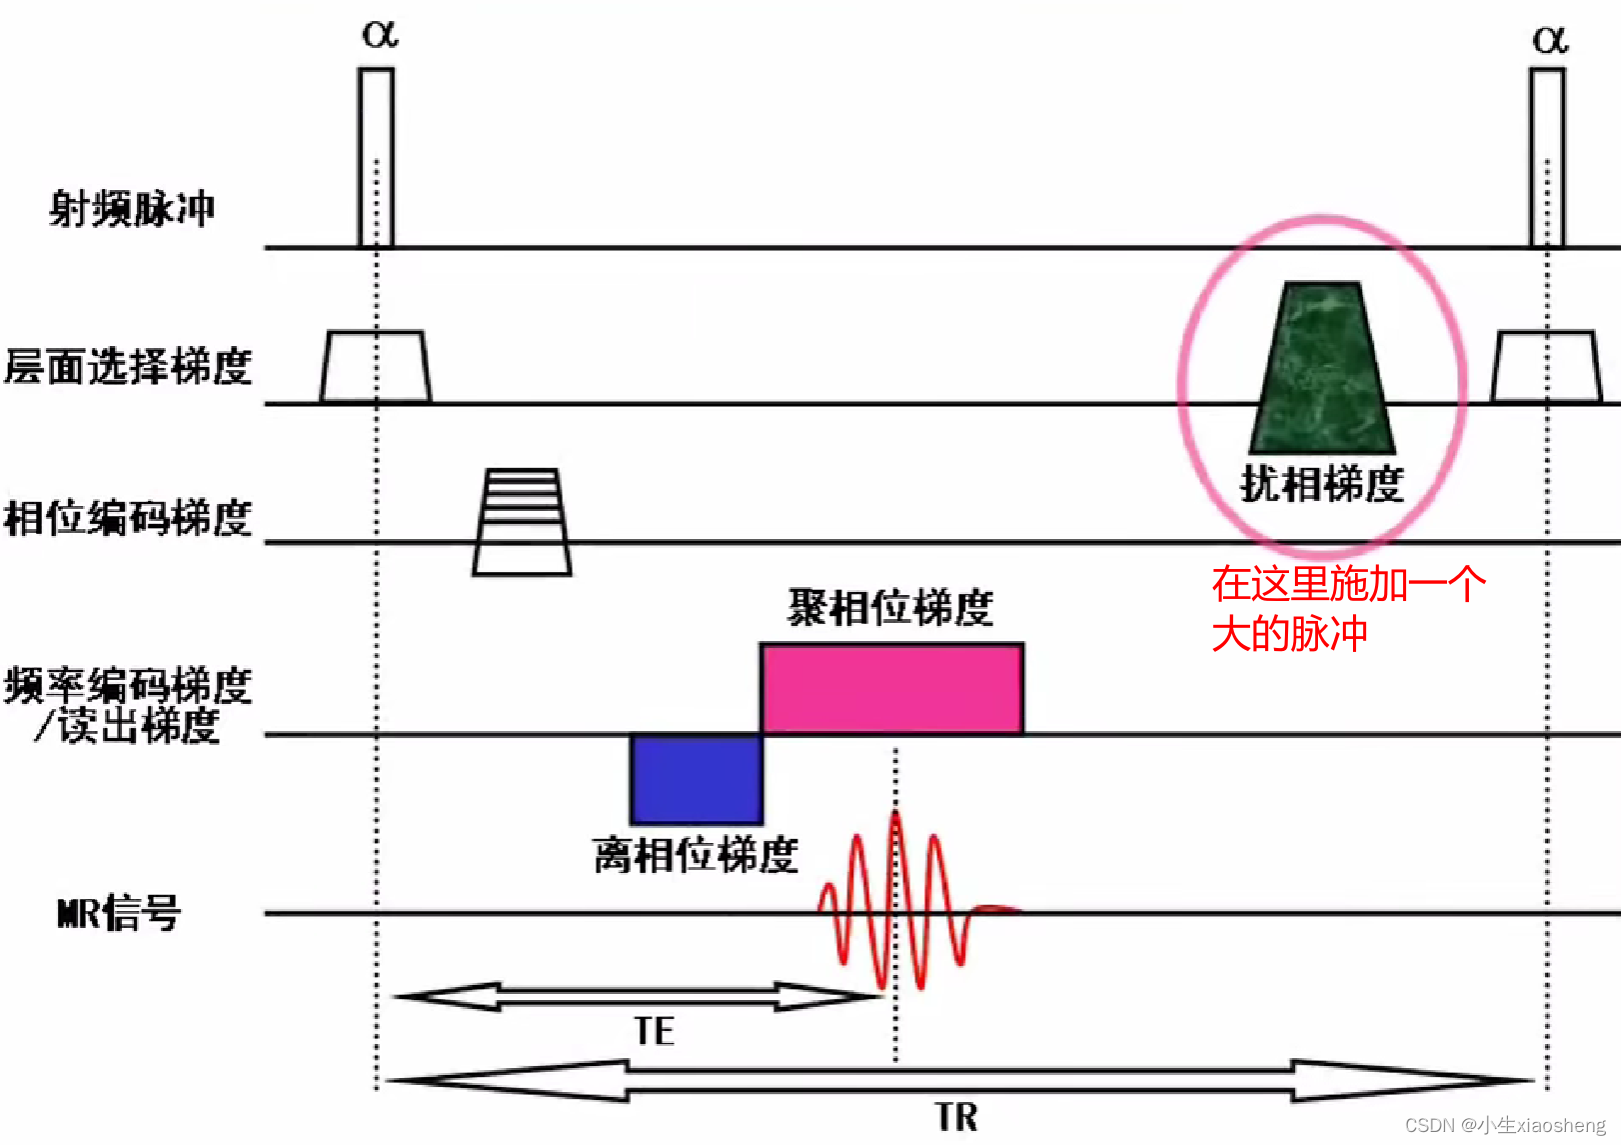

在SSFP成像中,如果每个SSFP-REF能够保持稳态,那么就可以利用这些回波信号来重建高质量的MRI图像。然而,由于各种因素的影响(如磁场不均匀性、组织特性等),SSFP-REF可能会发生变化,这可能会导致图像伪影(如带状伪影)的出现。而扰相主要用于提高成像速度和消除图像伪影。扰相技术的主要目的是在前一次射频脉冲(α脉冲)的MR信号采集后,对组织中的质子群的相位进行干扰,使其失相位加快,从而消除残留的横向磁化矢量。

1).梯度扰相(gradient spoiling):通过施加扰相位梯度场,人为地增加磁场的不均匀性,使质子失相位加快,从而消除残留的横向磁化矢量。扰相梯度场可以只施加于层面选择方向,也可以在层面选择、相位编码和频率编码三个方向都施加。